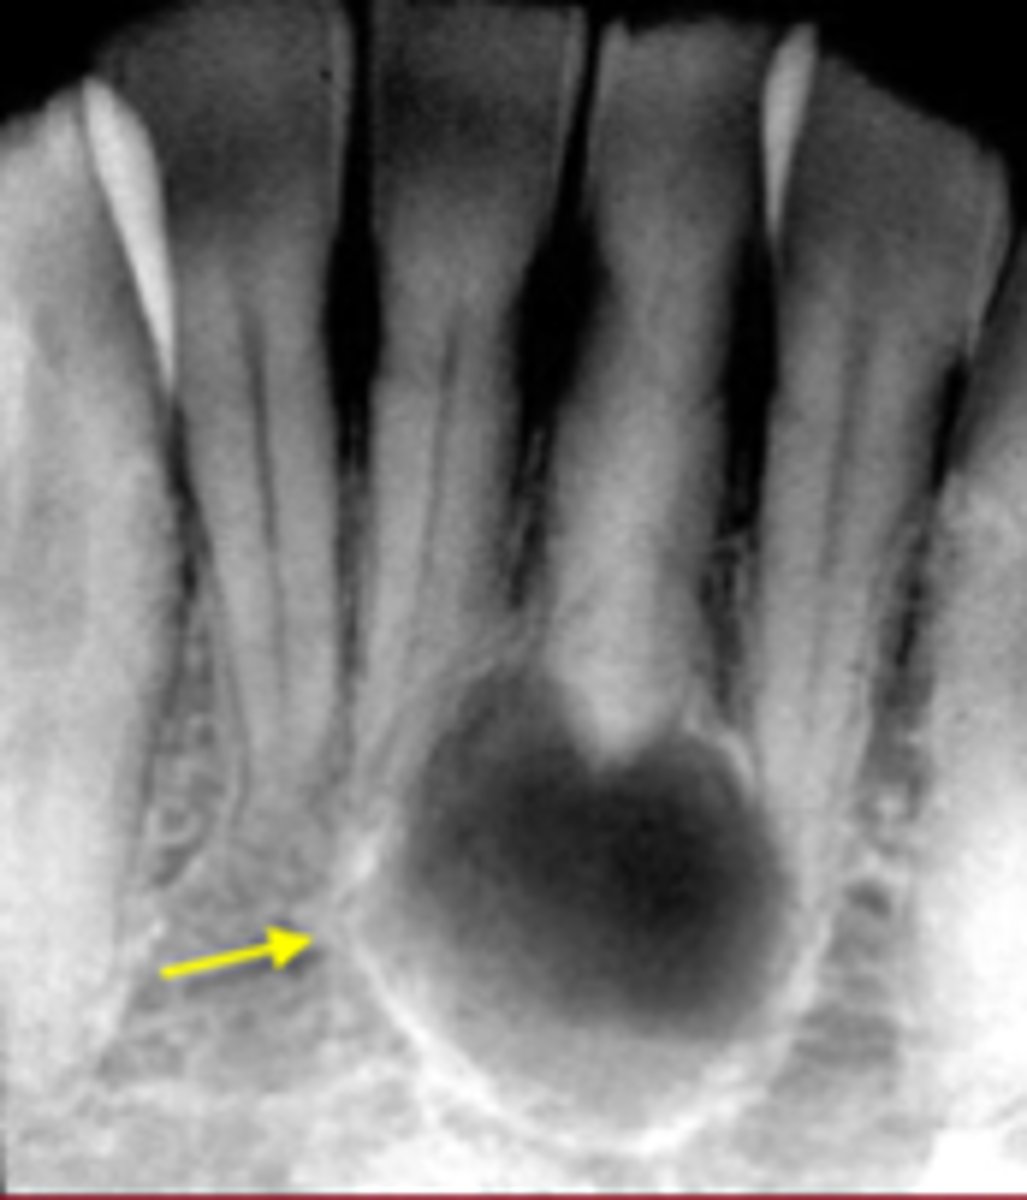

how would you describe this lesion?

A. well-defined, periapical radiolucent lesion associated with #24 and 25

B. ill-defined, periapical radiolucent lesion associated with #24 and 25

C. well- defined, multilocular periapical lesion associated with tooth number 24 and 25

D. mixed density, periapical lesion associated with teeth number 24 and 25

- Also note loss of apical lamina dura of 24, 25

What category would this lesion be part of?

Dysplasia

What would be a differential diagnosis for this lesion?

PCOD (stage 1)